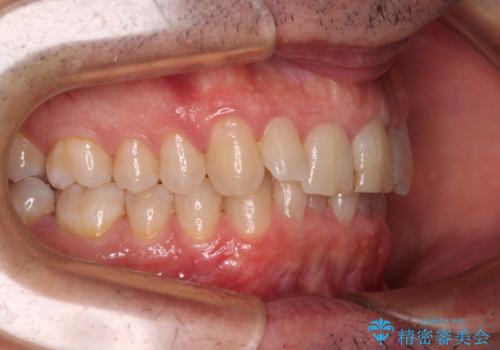

【モニター】前歯のデコボコを治したい インビザライン矯正治療

- 患者様

- 40代男性

- 矯正装置

- インビザライン

- 前歯のデコボコを気にして来院された患者様です。

インビザラインでもワイヤー装置でも対応可能でしたが、仕事の都合で来院回数を減らしたいとのことでインビザラインによる矯正治療を選択されました。

著しく咬合力が強いため、奥歯がしっかりと噛めずに治療が長引くことが懸念されました。

1セット目のインビザラインを使用した際には左右ともに大臼歯が咬み合っていなかったのですが、2セット目できっちりと仕上げることができました。